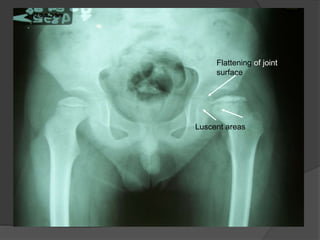

X-ray of head of femur (AVN)

 Crescent Sign

 Snowcapping

 Areas of lucency

 Flattening of joint surface

Crescent Sign

Luscent areas

Flattening of joint

surface

X-ray of headof femur (AVN)  Crescent Sign  Snowcapping  Areas of lucency  Flattening of joint surface